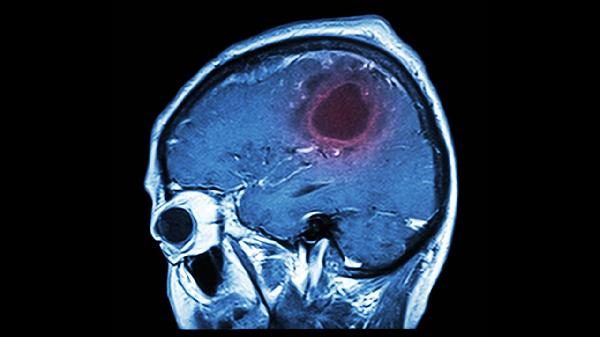

脑动脉硬化、早期阿尔茨海默病等器质性疾病会导致认知功能下降,常伴随头痛、定向障碍等症状。需通过头颅MRI、脑电图等检查确诊,临床常用多奈哌齐、美金刚等神经保护剂治疗,配合经颅磁刺激等物理疗法。